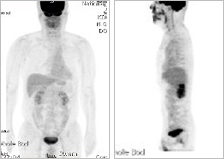

| 14 | 흉부CT 검사 | 검진동 4층 | 약 5~10분 | 폐암, 기관지염, 천식, 기관지확장증 등 |     |

| 15 | 흉부촬영검사 | 검진동 4층 | 약 2~5분 | 폐결핵, 폐렴, 심장비대 등 흉부질환 |  |

| 16 | 복부 초음파 검사 | 검진동 4층 | 약 15분 | 간, 담도, 신장, 췌장, 비장 등의 질환 |   |